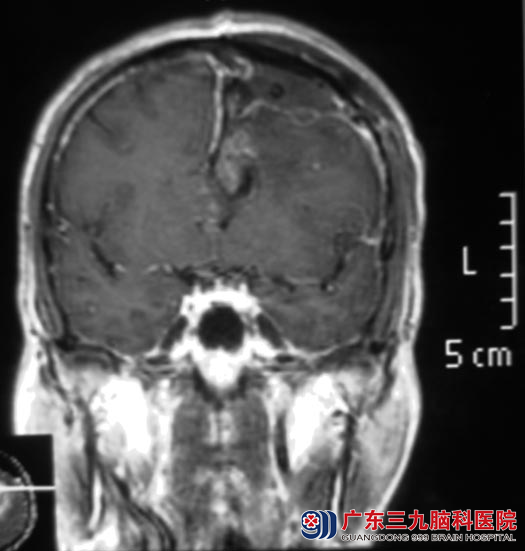

广东三九脑科医院头颅MR检查提示:左侧额叶深层白质区胼胝体上方占位病灶,范围约34.1mm×49.1mm×29.6mm,周围示大片状低信号水肿影,胼胝体明显受压,提示偏恶性肿瘤性病变,高级别星形细胞瘤或转移瘤可能。

家里人商量后,同意手术治疗。9月26日,综合神经外科 鲁明主任主刀,在唤醒麻醉下行左额叶肿瘤切除术,术中导航定位肿瘤位置,皮层诱发电定位语言及肢体运动中枢,避开脑皮层功能区,唤醒赵先生,在语言及肢体运动配合下,切除额上回部分脑组织,深度约3cm见灰白色肿瘤组织,质软,血供丰富,予显微镜下用超声刀逐步切除,镜下全切肿瘤,手术顺利。术后赵先生右侧肢体乏力较术前明显好转,已能自行活动。术后病理结果:胶质母细胞瘤(WHO IV级)。后期赵先生仍需接受进一步的放化疗治疗。